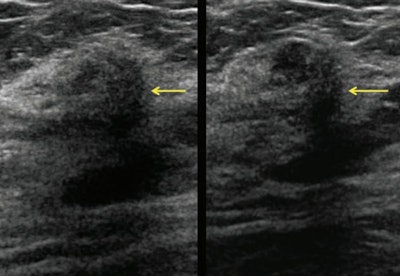

Invasive lobular carcinomas averaged 15% to 20% of malignancies in the studies in which the cancers were only seen on screening ultrasound. In nearly all the published studies, the mean invasive cancer size ranged from 7 mm to 13 mm.

In studies in which technologists conducted the ultrasound, the mean invasive cancer size ranged from 9 mm to 14 mm.

"These are the important cancers to find with screening -- invasive cancers caught early require minimal treatment and have an excellent prognosis, and this is why screening reduces deaths from breast cancer," Berg told AuntMinnie.com. "It is also important that automated screening breast ultrasound showed similar performance."